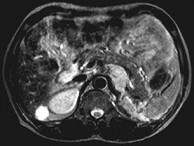

问题 女,34岁,无意中发现血压升高4个月就诊,行CT检查,如图所示,下列说法正确的是()

选项 A.CT示左侧肾上腺区可见一等密度块影,边界清楚 B.增强扫描,该病灶周边明显强化,中心处强化不明显 C.考虑为左肾上腺腺瘤 D.考虑为左肾上腺嗜铬细胞瘤 E.考虑为左肾上腺转移瘤

答案 ABD